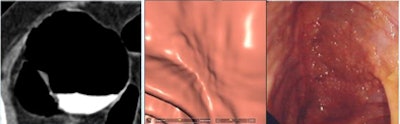

Two lesions were detected only by CAD and were not reported by the radiologists as flat due to low conspicuity. Two lesions with heights < 1 mm weren't seen at CTC but were detected at conventional colonoscopy.

| Two lesions with heights < 1 mm weren't seen at CTC despite optimal technology. Above, "carpet" lesion not visualized at CTC. |